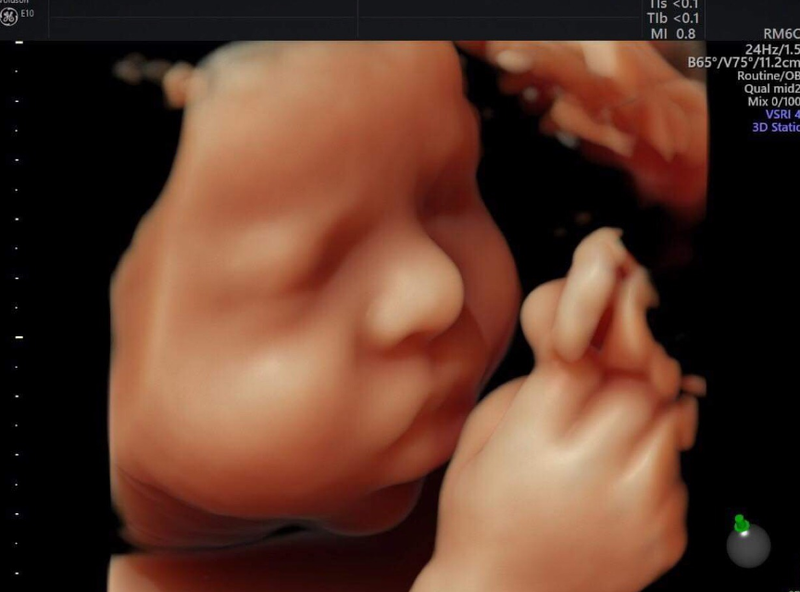

Thai nhi từ 20 đến 42 tuần tuổi: Chiều dài phôi thai được đo từ đầu đến gót chân. Thông qua các hình ảnh siêu âm vào giai đoạn này, bà bầu có thể quan sát thấy kích thước cũng như cân nặng của thai nhi tăng dần đều.

Một cách khác để kiểm soát cân nặng của thai nhi là khám thai định kỳ. Bác sĩ có thể phát hiện ra những vấn đề bất thường của bé thông qua các chỉ số đo đạc, siêu âm thai, từ đó có giải pháp sớm khắc phục.